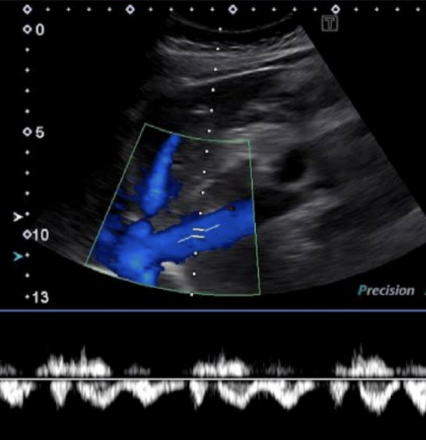

HVs Doppler waveform

complex, spontaneous, above and below baseline

variations with respiration cycle

IVC Doppler waveform